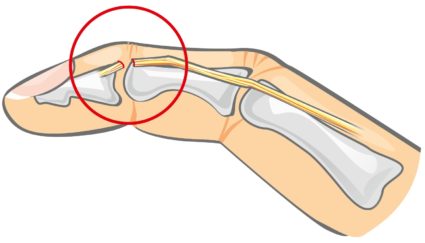

Артрозом называется заболевание суставов пальцев и стоп ног, которое характеризуется поражением хрящей. Данное заболевание является распространенной причиной потери работоспособности. Человека, которому был поставлен диагноз «артроз», мучают сильные боли в суставах. А ограниченность движений конечностей и нарушенная мелкая моторика создают множество проблем. Данное заболевание не всегда получается вылечить полностью, но, учитывая возможности современной медицины, можно не только снять некоторые симптомы, но и затормозить развитие недуга, не допуская при этом деформации пальцев и стоп ног.

Любая форма артроза (полиостеоартроз, остеоартроз) начинается с того, что в подхрящевых слоях надкостницы стопы или пальцев нарушается кровоток. Это приводит к плохому питанию хрящевой ткани. В результате хрящ становится тонким и менее эластичным, а его поверхность покрывается трещинами. Снижается объем синовиальной жидкости, а сильное трение костей приводит к воспалению пораженных суставов стоп ног и пальцев. Если вовремя не начать лечить, то заболевание начинает прогрессировать.

Прогрессирующий артроз (остеоартроз или полиостеоартроз) — достаточно опасная болезнь. Если при первых признаках ее не начинают лечить, то стопы ног и фаланги пальцев приобретают уродливую форму и утрачивают подвижность.

Недуг в первую очередь поражает мелкие суставы между фалангами пальцев. Ткани, задетые недугом, теряют влагу и покрываются множеством мелких трещин. В группу риска попадают женщины в возрасте от 40 лет.